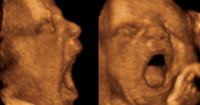

6. Gravidanza e sbadiglio | Studio Unife apre nuove prospettive sul comportamento prenatale

Si trova in Notizie / 2026 / Scienza, cultura e ricerca

Gravidanza e sbadiglio | Studio Unife apre nuove prospettive sul comportamento prenatale